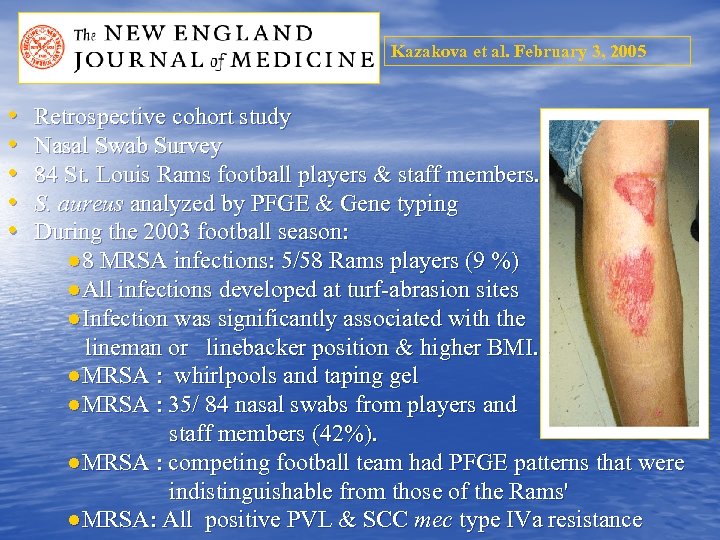

Kazakova et al. February 3, 2005 • • • Retrospective cohort study Nasal Swab Survey 84 St. Louis Rams football players & staff members. S. aureus analyzed by PFGE & Gene typing During the 2003 football season: ● 8 MRSA infections: 5/58 Rams players (9 %) ●All infections developed at turf-abrasion sites ●Infection was significantly associated with the lineman or linebacker position & higher BMI. ●MRSA : whirlpools and taping gel ●MRSA : 35/ 84 nasal swabs from players and staff members (42%). ●MRSA : competing football team had PFGE patterns that were indistinguishable from those of the Rams' ●MRSA: All positive PVL & SCC mec type IVa resistance

Kazakova et al. February 3, 2005 • • • Retrospective cohort study Nasal Swab Survey 84 St. Louis Rams football players & staff members. S. aureus analyzed by PFGE & Gene typing During the 2003 football season: ● 8 MRSA infections: 5/58 Rams players (9 %) ●All infections developed at turf-abrasion sites ●Infection was significantly associated with the lineman or linebacker position & higher BMI. ●MRSA : whirlpools and taping gel ●MRSA : 35/ 84 nasal swabs from players and staff members (42%). ●MRSA : competing football team had PFGE patterns that were indistinguishable from those of the Rams' ●MRSA: All positive PVL & SCC mec type IVa resistance